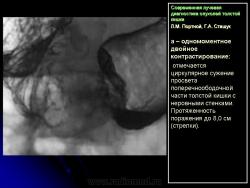

В 1961 г. Wellin предложил методику рентгенологического исследования толстой кишки, названную автором одномоментным двойным контрастированием толстой кишки (ОДКТК). Основное отличие ее от классической ирригоскопии состоит в том, что для исследования толстой кишки используется значительно меньшее количество бариевой взвеси и сразу же, по мере ее введения в дистальные отделы кишки, дальнейшее продвижение осуществляется специальным одноразовым устройством с помощью воздуха, вводимого под контролем рентгенотелевидения с учетом клинических особенностей пациента. Опыт многих исследователей и наш личный опыт указывают, что такие предосторожности при исследовании обусловлены не возможностью осложнений, а тем, что нередко быстрое контрастирование кишки может вызвать спазм отдельных ее участков и тем самым уменьшить его эффективность. Как правило, для исследования всех отделов толстой кишки, так же как и приирригоскопии, применяется стандартизованная методика с использованием тех же пяти проекций. Фиксация изображения осуществляется на рентгеновскую пленку средних размеров 18 х 24, 24 х 30 см. Основными достоинствами ОДКТК следует считать его высокую диагностическую эффективность, методическую простоту и возможность использования при скрининговых обследованиях групп риска по раку толстой кишки. В ОДКТК удачно сочетаются фазы “тугого” наполнения и двойного контрастирования – основные элементы, позволяющие фиксировать внутристеночную инфильтрацию кишки в ее начальных проявлениях с помощью определения состояния контура кишки и толщины стенки. Двойное контрастирование позволяет получить исчерпывающую информацию о слизистой кишки, которая при отсутствии в ней изменений (небольших полиповидных образований, изъязвлений и др.) должна быть полностью разглажена и лишена складчатости (рис. 1).

При одномоментном двойном контрастирова нии толстой кишки:

1) утолщение стенки, неровность контура и сужение просвета одного из участков кишки (рис. 5);